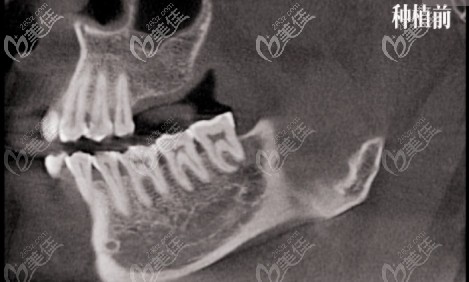

瑞士ITI種植體

種植不傷臨近天然牙,種植完成時間短 瑞士ITI種植體價格:¥15000~20000元